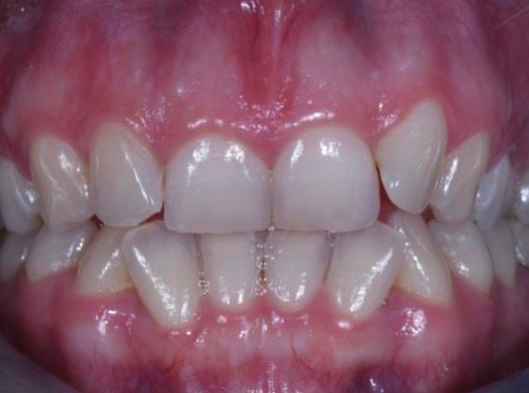

Severe Crowding

Upper front teeth realigned using invisalign series of aligners without removing any teeth.